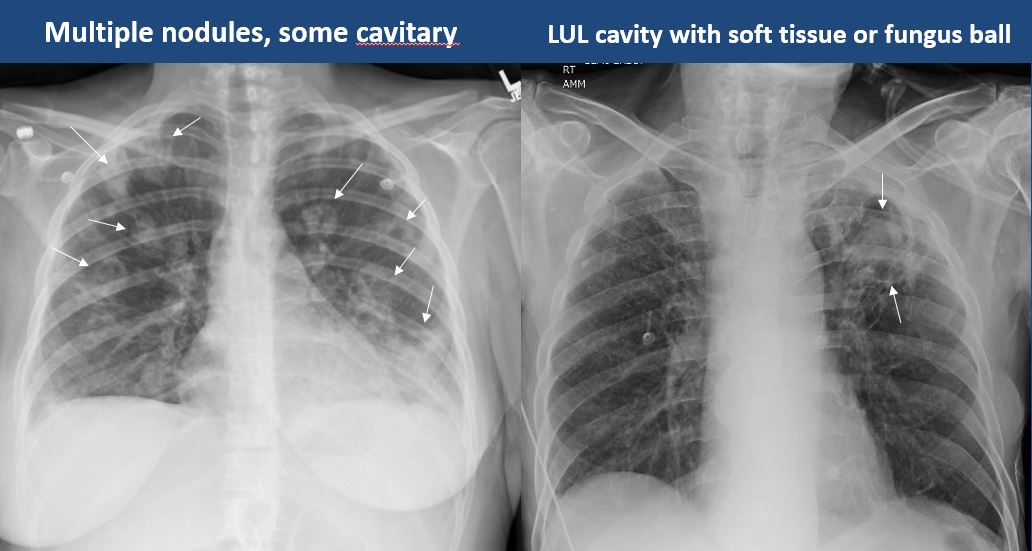

There is cavitary or cystic disease with or without air fluid levels or soft tissue nodularity. |

no | NA |